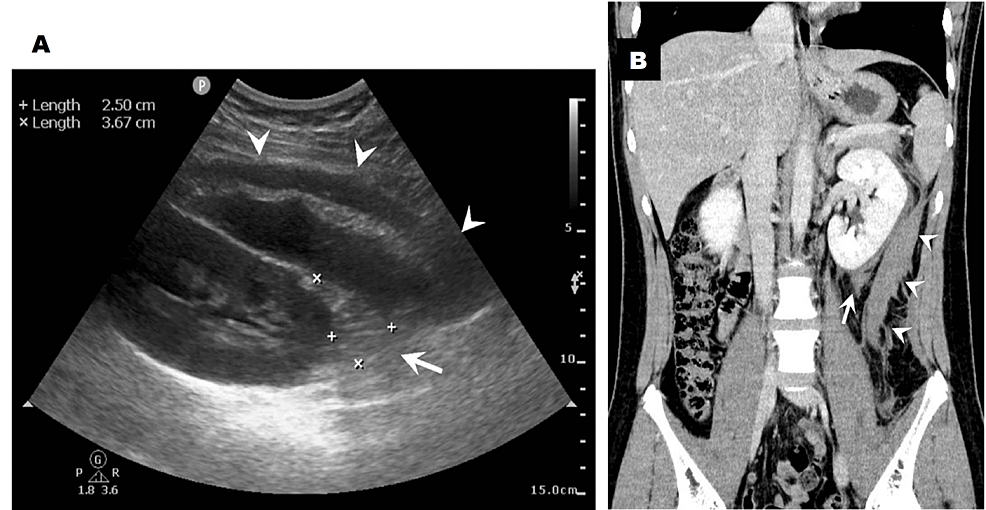

From www.ccjm.org

Page kidney after a renal biopsy Cleveland Clinic Journal of Medicine Aspirin Post Renal Biopsy We conducted a single center retrospective study comparing the risk of complications after percutaneous native kidney. The 2 nonrandomized primary studies in prb patients managed with and without aspirin found no difference in major bleeds but a higher risk. Therefore, aspirin is routinely withheld in. To decrease the risk of bleeding, you should stop taking medicines that increase the risk. Aspirin Post Renal Biopsy.

From www.cureus.com

Postrenal Biopsy Retroperitoneal Haematoma by Decreased Aspirin Post Renal Biopsy The 2 nonrandomized primary studies in prb patients managed with and without aspirin found no difference in major bleeds but a higher risk. We conducted a single center retrospective study comparing the risk of complications after percutaneous native kidney. Therefore, aspirin is routinely withheld in. To decrease the risk of bleeding, you should stop taking medicines that increase the risk. Aspirin Post Renal Biopsy.

From pocusjournal.com

Point of Care Ultrasound in Monitoring of PostRenal Biopsy Bleeding Aspirin Post Renal Biopsy We conducted a single center retrospective study comparing the risk of complications after percutaneous native kidney. Therefore, aspirin is routinely withheld in. The 2 nonrandomized primary studies in prb patients managed with and without aspirin found no difference in major bleeds but a higher risk. 1 scope of the guideline. To decrease the risk of bleeding, you should stop taking. Aspirin Post Renal Biopsy.